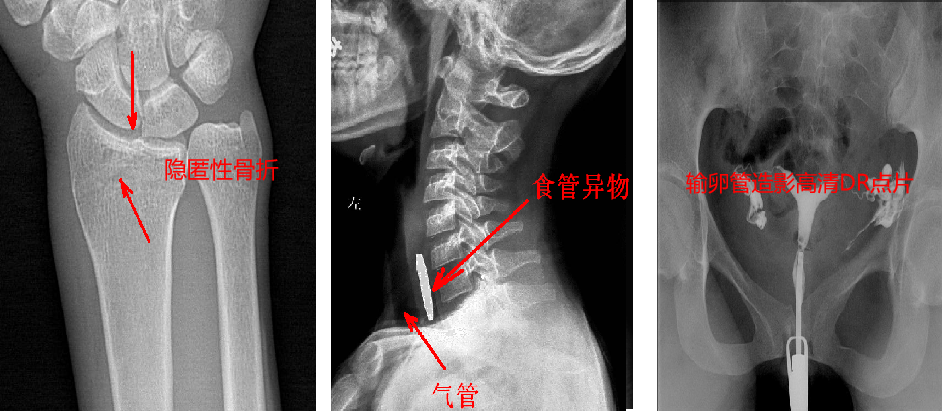

靜態(tài)DR最大的缺陷來(lái)自于盲拍,因此造成誤診發(fā)生率高,是保證診斷準(zhǔn)確性的巨大阻礙因素。在靜態(tài)拍片中,部分特殊病灶容易被遮掩而導(dǎo)致漏診,在一些特殊造影上需要憑借醫(yī)生的臨床經(jīng)驗(yàn)才能獲取有效影像。而動(dòng)態(tài)DR依靠可視化高速高清點(diǎn)片功能,改變了傳統(tǒng)的盲拍模式。動(dòng)態(tài)DR在低劑量數(shù)字透視的情況下,能夠進(jìn)行疑似病灶部位點(diǎn)片,極速精準(zhǔn)獲取有效信息,同時(shí)可即時(shí)回放視頻信息,在臨床上極大地提高了病變的檢出率,降低漏診誤診。

與此同時(shí),動(dòng)態(tài)DR的成像視野與精度也勝于靜態(tài)DR。動(dòng)態(tài) DR17×17 英寸方形幅面進(jìn)行動(dòng)態(tài)成像,能夠?qū)鹘y(tǒng)動(dòng)態(tài)造影幅面小的問(wèn)題全部解決,同時(shí)由于幅面較大,臨床操作技師能夠在一個(gè)大的幅面下觀察診斷,當(dāng)看到病變部位時(shí)實(shí)時(shí)高清點(diǎn)片,從而很好地捕捉到病變點(diǎn),也大大降低了檢查時(shí)間。